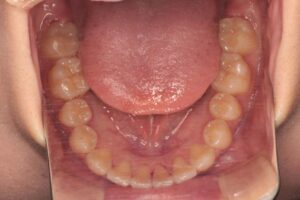

口腔内所見としては上下顎前歯部の叢生も認められますが、非抜歯での治療が可能であると判断しました。

治療中の口腔内写真では埋伏犬歯を牽引する部位にオープンコイルを装着し牽引スペースを確保しつつ、埋伏犬歯は開窓手術後、ボタンを装着して牽引しているところです。

歯根の平行性も良好です。口腔内写真から前歯部叢生も改善したことがわかります。反省点というか、惜しいと思うのは正中線を合わせる時間がなかったことでしょうか。治療期間は1年6か月でしたから、あと6か月ほど時間があれば合わせられたと思うのですがこの辺りは患者様のご希望との擦り合わせの部分もあって難しいところです。もし時間的余裕があれば顎間ゴムと併用して下顎左側部に歯科矯正用アンカースクリューを植立して下顎正中を左側に移動したと思います。